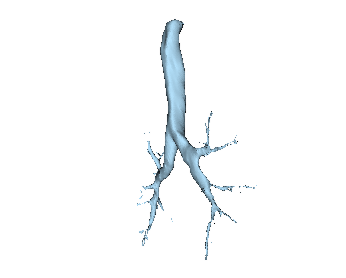

In many cases, the computational domain is derived from patient-specific anatomy. It starts with a medical image: MRI, CT, OCT, IVUS, etc. This provides a 3D volume from which a specific anatomy must be segmented. The segmentation, also known as a label map, is essentially a subset of voxels that are considered part of the anatomy. It is a volumetric mask that represents the object to be modeled (a heart, a vessel, an airway, etc.).

Before generating a 3D volume mesh for CFD, the segmentation undergoes preprocessing for refinement including ensuring a watertight mesh can be generated for simulation and face/surface labeling. The algorithms for doing this are often anatomy dependent, and the identification of faces for boundary conditions often relies on custom scripts. When dealing with many medical images, both manual segmentation and custom scripting can quickly become expensive and time consuming.

SimVascular is an open source software package that provides an end-to-end pipeline for cardiovascular CFD modeling. It is specialized for cardiovascular applications and less general-purpose than 3D Slicer, but it is an exception to the “no all-in-one solutions” comment above. SimVascular provides within a single environment tools for segmentation, model construction, and finite element solvers for cardiac modeling and vascular hemodynamics.

After isolating the anatomy of interest and processing it into a CFD-ready mesh, one needs to specify boundary and initial conditions. These typically come from a combination of measurements and assumptions about the behavior downstream of the region of interest. Pulse can be used to create a closed-loop system by using a multi-physics, multi-scale approach to modeling the human body. The Pulse Physiology Engine is a computational physiology simulation that is composed of numerical models representing the different body systems, feedback mechanisms and interactions between the systems, pharmacokinetics/pharmacodynamics, and medical equipment. Major systems are modeled as zero-dimensional lumped-parameter circuit analogs. This means that there is no spatial component; instead, systems are analogous to electrical circuits with resistors, capacitors, pressure sources, and valves, together giving rise to a system of differential equations. Using Pulse to provide outlet boundary conditions allows CFD models to include dynamic downstream impacts in the boundary conditions.